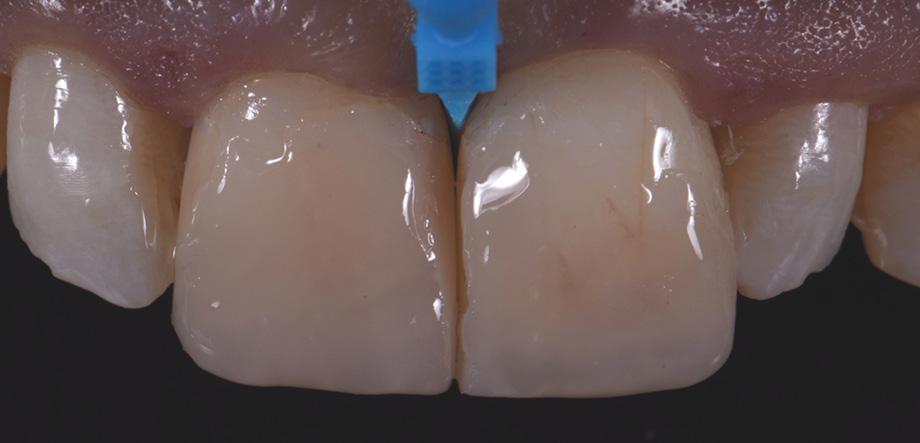

This case study presents the clinical management of a patient who presented with an existing failed anterior composite, requiring a Class IV direct composite replacement. The restoration aimed to achieve seamless integration with the natural dentition while restoring form and function.

Figure 7 – 2-week review demonstrating the complete optical and functional G-ænial™ A’CHORD restoration on the tooth 21.

5 - A chromatic body shade, G-ænial™ A’CHORD shade A2 was then applied and extended beyond the bevel to mask the transition line. Internal anatomy in the incisal third was also sculpted and formed in this increment of composite resin. White tints, Essentia White Modifier (WM) was then utilised to accentuate the mamelons and to replicate similar characteristics present in the adjacent right central incisor.

Figure 6 - A final translucent shade of G-ænial™ A’CHORD shade JE was then placed to bring the anatomy to full contour.